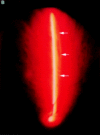

Aims: To identify variations in posterior vitreous detachment (PVD) and establish a clinical classification system for PVD.

Methods: 400 consecutive eyes were examined using biomicroscopy and vitreous photography and classified the PVD variations-complete PVD with collapse, complete PVD without collapse, partial PVD with thickened posterior vitreous cortex (TPVC), or partial PVD without TPVC.